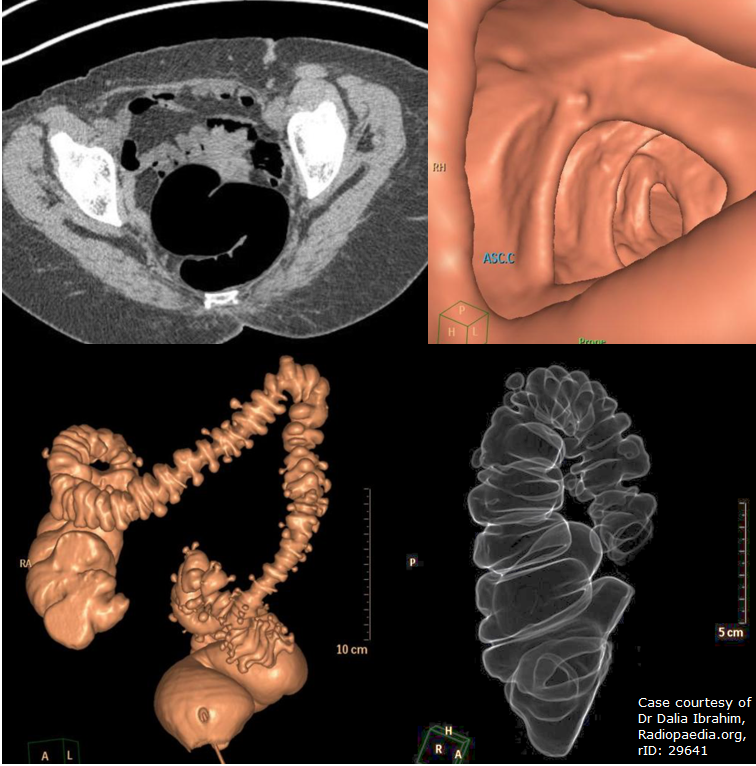

Cost Of Ct Colonoscopy . A virtual colonoscopy is a procedure that uses ct scans to look inside your large bowel. Many people choose a colonoscopy, the gold standard for colorectal cancer screening and prevention. It’s also known as ct colonography or ct colonoscopy. Just like with a colonoscopy, patients need to take laxative medications the night before to empty the. According to the american cancer society, everyone aged 45 to 75 should be screened for colorectal cancer. A ct scan is used to visualize your rectum and entire colon. Ct colonography can provide information about the colon that would usually only be obtainable by doing a colonoscopy.